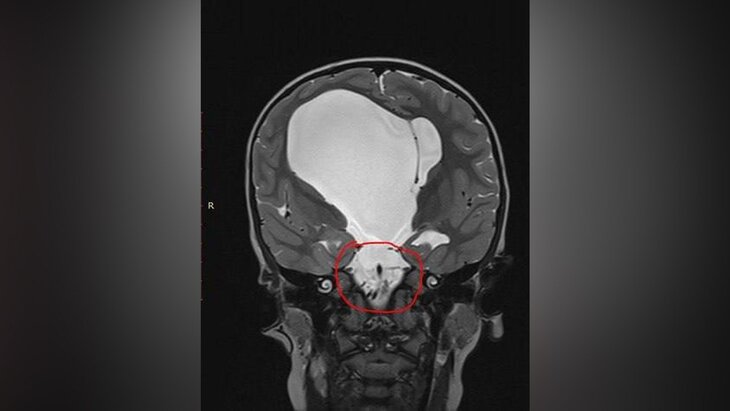

Врачи ДНКЦ имени Л. М. Рошаля удалили 4-летнему ребенку кистозное образование правого полушария головного мозга размером около 10 сантиметров. Об этом сообщила пресс-служба подмосковного Минздрава.

Заведующий нейрохирургическим отделением Руслан Текоев рассказал, что киста механически раздражала и сдавливала окружающую ткань мозга, что становилось причиной эпилептических приступов.

В ходе операции медики сделали небольшой разрез на лбу пациента для доступа к полостям мозга. Через него они нашли, а затем удалили кисту, которая блокировала естественные пути оттока жидкости. Для восстановления циркуляции хирурги создали новое отверстие в дне желудочка мозга.